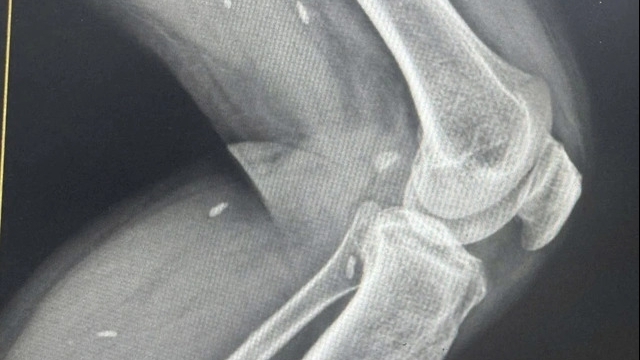

| Kết quả chụp DSA cho thấy túi phình động mạch cảnh trong bên trái |

Tại đây, các bác sĩ khám, cho làm xét nghiệm, chụp CT-Scan sọ não có bơm thuốc cản quang, phát hiện bà S. bị xuất huyết dưới nhện nghi do vỡ túi phình động mạch não. Xác định bệnh nhân đang trong tình trạng nguy kịch tính mạng, bệnh viện đã hội chẩn và chỉ định thực hiện can thiệp nội mạch bít túi phình để ngăn chặn xuất huyết não tiếp diễn.

Ngay sau đó, bệnh nhân được các bác sĩ tiến hành chụp mạch máu não, phát hiện túi phình động mạch cảnh trong bên trái kích thước 3,5x3cm. Ê kíp can thiệp quyết định xử trí bằng phương pháp thả coil (vật liệu gây bít túi phình) và sau đó đặt 1 stent để chẹn cổ túi phình.